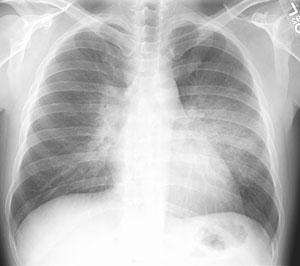

Scott WilliamsPETPET > PET tumor imaging > Lung CancerApril 2, 2002AutoimmuneAutoimmune > EGApril 2, 2002PETPET > PET tumor imaging > Lung Cancer > LUNG CANCERApril 2, 2002Cardiac ImagingCardiovascular > Thallium > FindingsApril 2, 2002AutoimmuneAutoimmune > DrugsApril 2, 2002GenitourinaryPancreatic-Renal Transplant:April 2, 2002Tramatic Thorax InjuriesTrauma > DiaphragmApril 2, 2002CardiacCardiac > CongenitalApril 2, 2002AutoimmuneAutoimmune > Proteinosis > Images > Case2April 2, 2002Infection-InflamationInfection-Inflammation > Genitourinary > Adrenal imagingApril 2, 2002Previous PagePage 55 of 265Next PageTop StoriesCTNew benchmark helps monitor cumulative CT radiation doseThe findings highlight the need for systematic dose tracking and rigorous justification of imaging.Radiation Oncology/TherapyStudy questions routine use of radiotherapy after bone surgeryUltrasoundCEUS outshines color Doppler imaging for indeterminate kidney lesionsWomens ImagingWomen's Imaging MinnieCast, Episode 2: Risk-based vs. annual mammography screening, part 1Digital X-RayChest x-rays reveal atherosclerosis in patients undergoing amputations